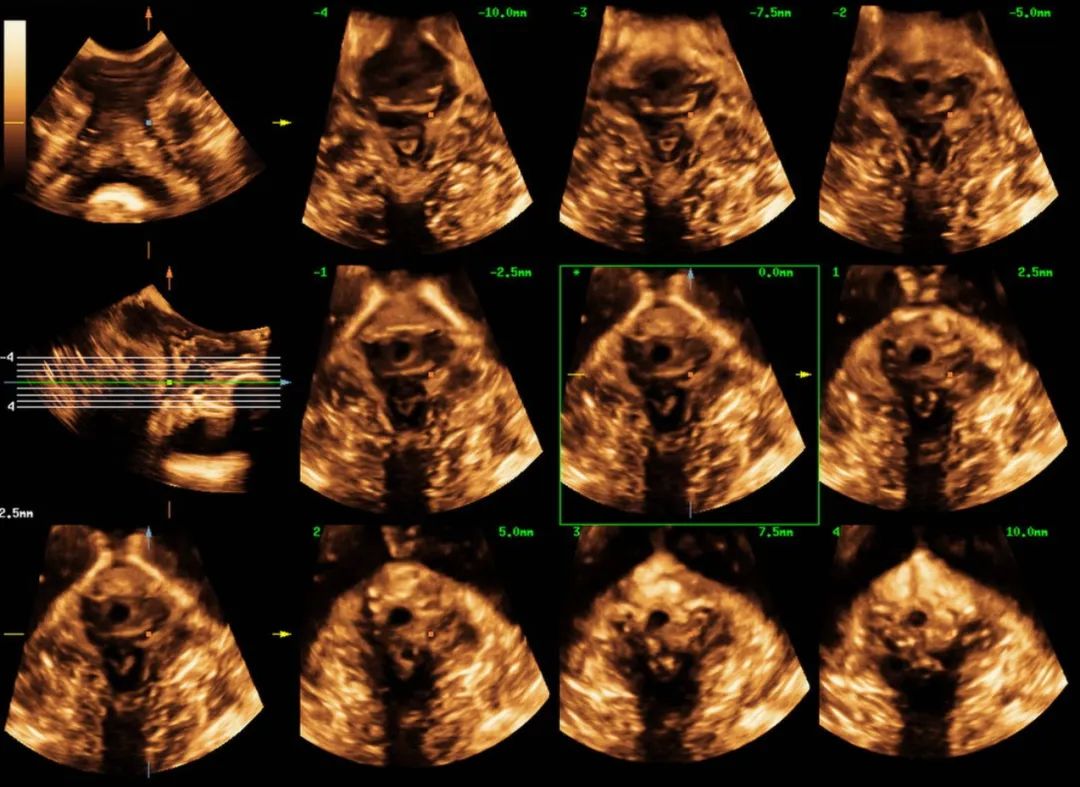

近日,54岁的黄女士因“尿失禁13年”来我院妇女保健科就诊,黄女士讲述了近十年来经常发生尿频尿急憋不住尿的经历,自己咳嗽、大笑或者长时间走路后便出现漏尿等尴尬症状,严重影响正常生活和社交活动。由于涉及隐私部位,怕人笑话,一开始她不敢跟身边的人说起这件事,能忍则忍。最近随着症状加重,难以忍受,终于来我院就诊。 在妇女保健科医师颜惠芳建议下,黄女士前往我院超声医学科行四维盆底超声检查,检查后发现黄女士有膀胱脱垂、子宫脱垂的现象,诊断为“压力性尿失禁”,终于找到漏尿的原因了,黄女士的治疗也可以针对性开展。 现实生活中,不少女性朋友也有过这样尴尬的经历,大笑、打喷嚏、咳嗽时尿液溢出外出时总想找厕所,私密处总有异物感,腰酸背痛,下腹坠胀,夫妻生活不和谐……种种难言之隐羞于说出口,却又如影随形。这一切的罪魁祸首很可能是——盆底功能障碍。 一、什么是盆底功能障碍 盆底功能障碍是指盆底肌肉、筋膜、韧带等支持结构受损而导致的一系列临床症候群,如压力性尿失禁、子宫等盆腔脏器脱垂、粪失禁、梗阻型便秘和性功能障碍等。妊娠和分娩是造成此病的首要原因,其中以经阴道分娩危险性最高,当前已成为影响全球妇女身心健康的五种最常见疾病之一,被称为“社交癌”。 二、为什么会发生盆底功能障碍? 怀孕、分娩、衰老、肥胖、长期便秘、慢性咳嗽、长期提重物等原因,都会导致盆底肌损伤,分娩是造成盆底肌损伤的主要原因。 通常胎儿头部大小都会大于正常的阴道大小,分娩时,阴道会受到胎儿头部的挤压而扩张,造成盆底肌肉损伤。双胎、巨大儿、分娩两次及以上的妈妈们,盆底肌受到的损伤通常会加倍。产后和围绝经期为高发期,被称为严重影响女性生活质量的五大慢性病之一。 三、什么是盆底超声? 盆底超声是使用特殊配置的超声仪器,利用二维图像、三维重建、动态四维显示联合应用,在患者静息、缩肛、valsalva不同状态下,直观了解盆底的静态、动态结构、显示耻骨联合、尿道、膀胱、阴道、宫颈、直肠壶腹及肛管等结构,从而评估盆底各脏器位置、功能,脏器脱垂情况、盆底肌有无损伤等。 盆底超声适应症: 1.盆腔脏器脱垂:膀胱脱垂、子宫脱垂、直肠膨出等; 2.排尿异常:压力性尿失禁、尿潴留、排尿困难等; 3.排便异常:粪失禁、便秘等; 4.性功能障碍:性交痛、性欲降低等; 5.慢性盆腔痛:下腹部疼痛、腰骶部或会阴痛等; 6.产后女性(42天至6个月)盆底功能障碍的早期筛查。 可疑盆底功能障碍性疾病人群、产后复查及围绝经期女性均建议行盆底超声检查。 超声医学科盆底超声检查介绍 我院超声科自2019年开展该项技术以来,已为500余名女性患者完成盆底超声检查。竭诚欢迎有需要的女性市民朋友来电咨询(025-56232058)或前往我院妇女保健科门诊就诊。 盆底超声检查时间:每周一和周二下午(具体以预约安排为准) 盆底超声检查医师简介 褚爱萍 科室副主任,主任医师(资格)。南京超声学会介入与腹部学组委员,从事超声诊断十余年,曾先后于江苏省人民医院及中大医院进修学习,并承担临床教学工作多年,擅长心脏、血管等超声诊断,对腹部、妇产、盆底、浅表、肌骨等亦有丰富的超声诊断经验。 汪金 中国共产党员,副主任医师,医学硕士,先后在四川大学华西医院、重庆医科大学附属儿童医院、北京301医院、朝阳医院等多家三甲医院进修、培训学习,取得了超声产前筛查、盆底超声、输卵管超声造影、肿瘤消融治疗等多项技术资质。 获省妇幼新技术引进三等奖,主持及参与省市级课题3项,发表论文数篇,其中SCI 3篇,授权国家专利9项。 钱露 副主任医师(资格),硕士研究生。毕业于徐州医科大学医学影像专业。从事超声诊断工作十余年,熟练掌握各种常见病、多发病的超声诊断,擅长妇科超声、盆底超声、产前筛查超声等工作。 李诺 主治医师,毕业于徐州医科大学临床医学专业,从事超声诊断工作数年,熟练掌握各种常见病,多发病的超声诊断工作,擅长妇科超声,盆底超声等超声诊断工作。